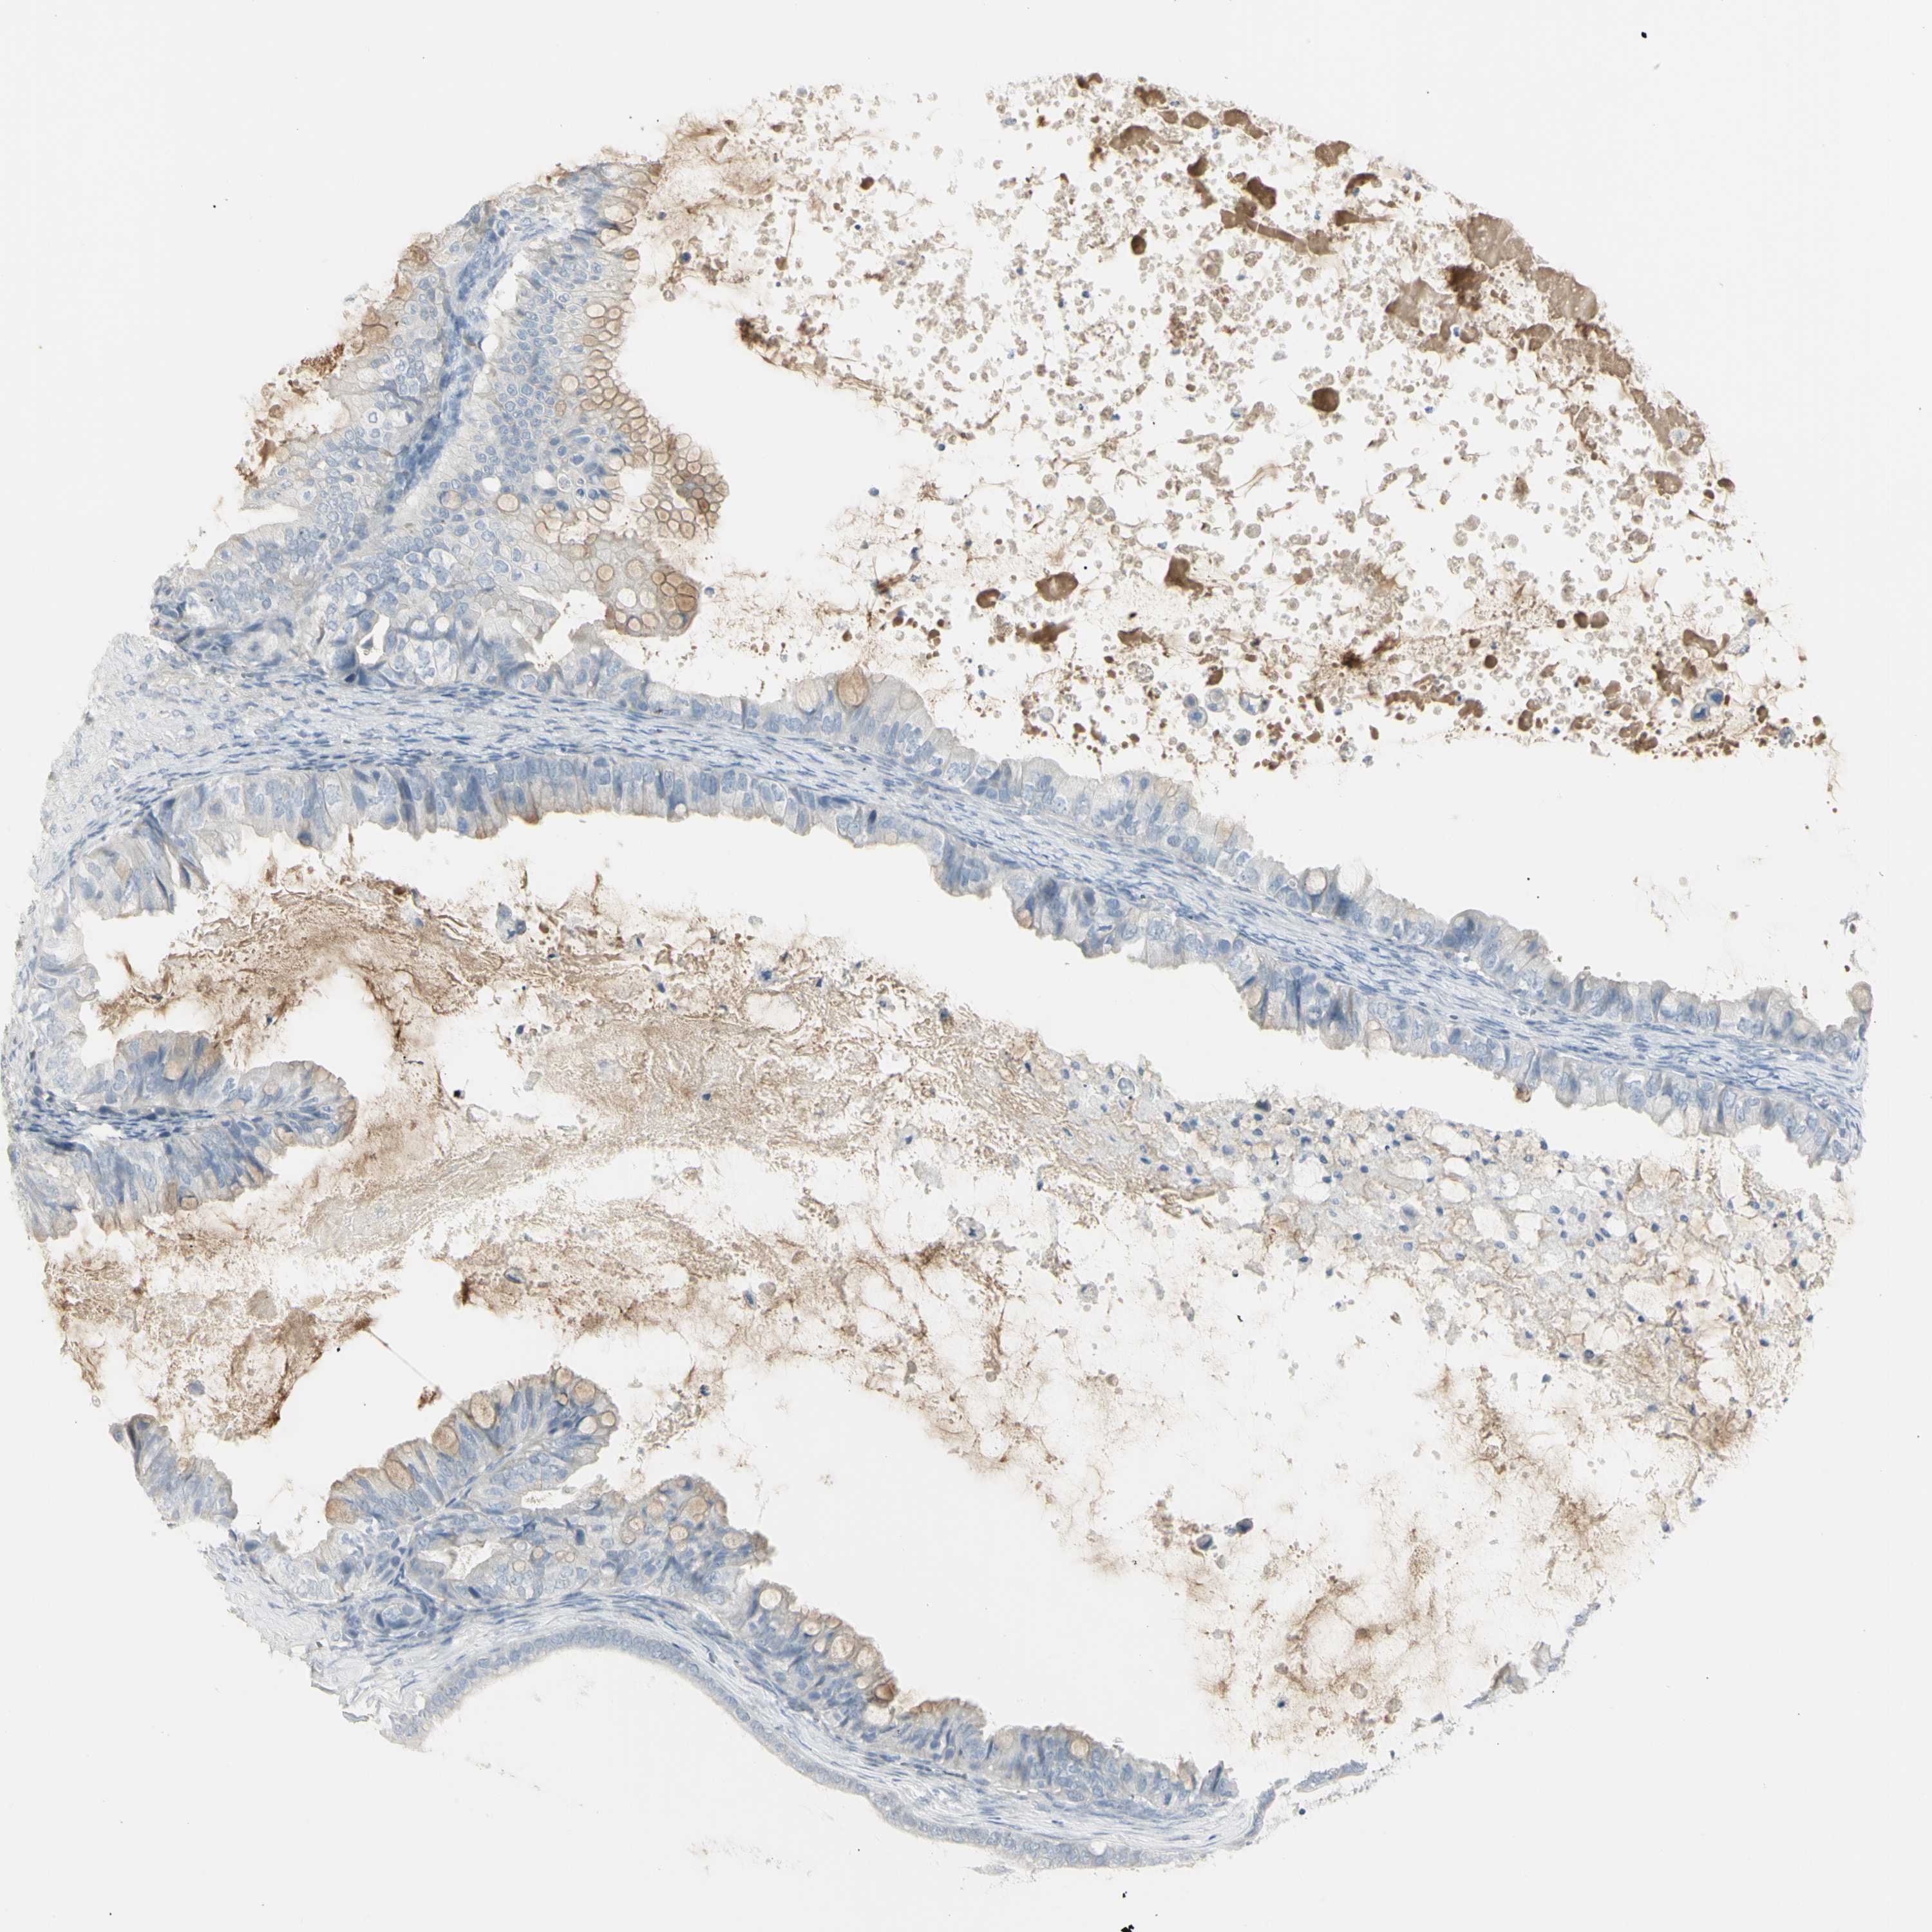

OVARIAN CANCER - Protein expressioni

A mouse-over function shows sample information and annotation data. Click on an image to view it in a full screen mode. Samples can be filtered based on level of antibody staining by selecting one or several of the following categories: high, medium, low and not detected. The assay and annotation is described here.

Note that samples used for immunohistochemistry by the Human Protein Atlas do not correspond to samples in the TCGA dataset.

Antibody stainingi

Antibody staining in the annotated cell types in the current human tissue is reported as not detected, low, medium, or high, based on conventional immunohistochemistry profiling in selected tissues. This score is based on the combination of the staining intensity and fraction of stained cells.

Each image is clickable and will lead to virtual microscopy that enables deeper exploration of all samples and also displays staining intensity scores, fraction scores and subcellular localization as well as patient and tissue information for each sample.

Antibody HPA009177

Antibody CAB002661

Staining

High

Medium

Low

Not detected

Intensity

Strong

Moderate

Weak

Negative

Quantity

>75%

75%-25%

<25%

None

Location

Nuclear

Cytoplasmic/membranous

Cytoplasmic/membranous,nuclear

Cystadenocarcinoma, serous, NOS

Carcinoma, endometroid

Cystadenocarcinoma, mucinous, NOS

Carcinoma, NOS